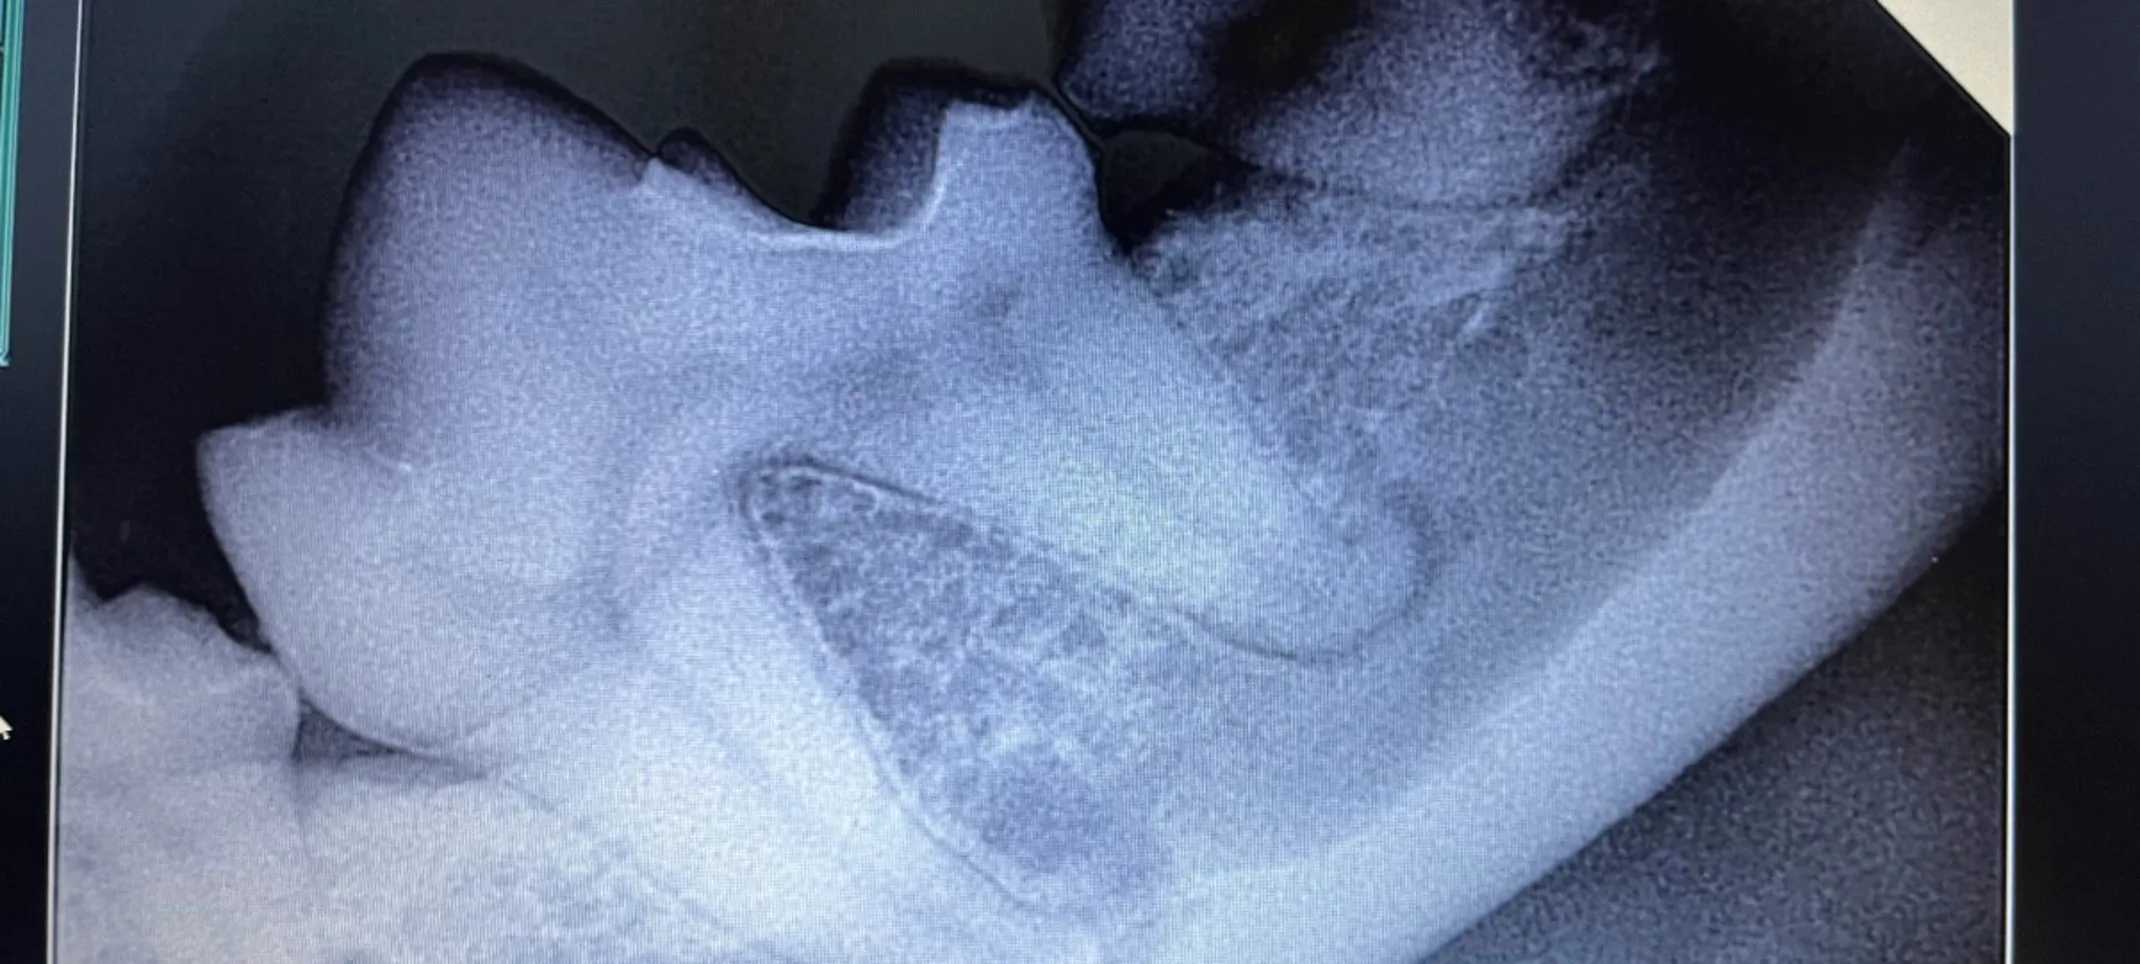

Dental Radiography

Your pet's dental health is very important which is why dental radiography is recommended to avoid or treat any potential disease.

Veterinary dental radiographs are performed to assist in diagnosing any existing dental diseases. Veterinary professionals take dental radiographs to be able to administer the proper care needed.

Dental radiographs are highly recommended during a dental cleaning to reveal any diseases a pet may encounter. A pet should also be brought in for a dental radiograph if they are experiencing any discomfort in their mouth. Signs of discomfort can include: eating irregularly, finicky eater, and/or loss of appetite.